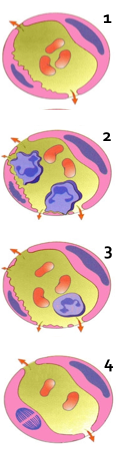

白细胞通过血管壁游出到血管外的过程称为白细胞渗出(leucocyte extravasation)。渗出的白细胞也称为炎性细胞,炎症反应的最重要功能是将白细胞输送到炎症局部。白细胞吞噬、消灭病原体,降解坏死组织和异己抗原;同时,也会通过释放化学介质、自由基和酶,介导组织损伤。因此,白细胞的渗出构成炎症反应的主要防御环节,是炎症反应最重要的特征。(白细胞的渗出机制)

白细胞的渗出及其在局部的防御作用是极为复杂的连续过程:(巨噬细胞的运动、白细胞渗出)

(1)白细胞边集和附壁:随着血管扩张、血管通透性增加和血流缓慢,白细胞进入边流,靠近血管壁,并沿内皮滚动。最后白细胞粘附于血管内皮细胞上。(下图A)

(2)白细胞粘附和游出: 目前已明确白细胞粘附和游出主要是由于其表面的粘附分子和内皮细胞受体结合引起的,化学介质和某些细胞因子可以调节这类粘附分子的表达和功能状况。这类粘附受体包括四种家族:选择素、免疫球蛋白、整合素和粘液样糖蛋白。(下图B-F)

(3)游出和趋化作用 :白细胞通过血管壁进入周围组织的过程称为游出(emigration)。粘附于内皮细胞表面的白细胞沿内皮表面缓慢移动,在内皮细胞连接处伸出伪足,整个白细胞逐渐以阿米巴样运动方式从内皮细胞缝隙游出,到达内皮细胞和基底膜之间,最终穿过基底膜到血管外(下图B-F)。中性粒细胞、单核细胞、淋巴细胞、嗜酸粒细胞和嗜碱粒细胞都是以此种阿米巴样运动方式主动游出的。